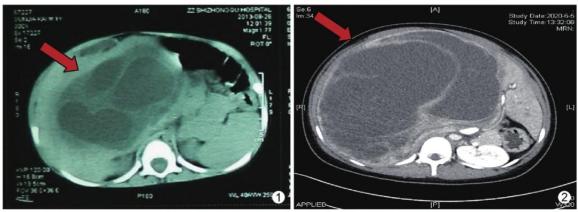

肝脏错构瘤是一种少见的肝脏良性肿瘤,临床缺乏特异表现,影像学认识不足导致术前误诊率高。

尽管是良性肿瘤,但有恶变为未分化型胚胎性肉瘤或血管肉瘤的可能。此病多无特征性的临床表现,主要因腹部进行性增大或触及腹部肿块就诊。

肝间叶性错构瘤。来源丨曹其伟,张亚洲,孙青.肝脏间叶性错构瘤临床病理特征分析[J].诊断病理学杂志.2022,29(06).下丘脑错构瘤是一种先天性的、非进展性(非进展性:不会随着时间而严重的,病情稳定的)瘤样肿块,是发生在在下丘脑下部或灰结节区的异位神经组织,主要症状是性早熟、癫痫等。